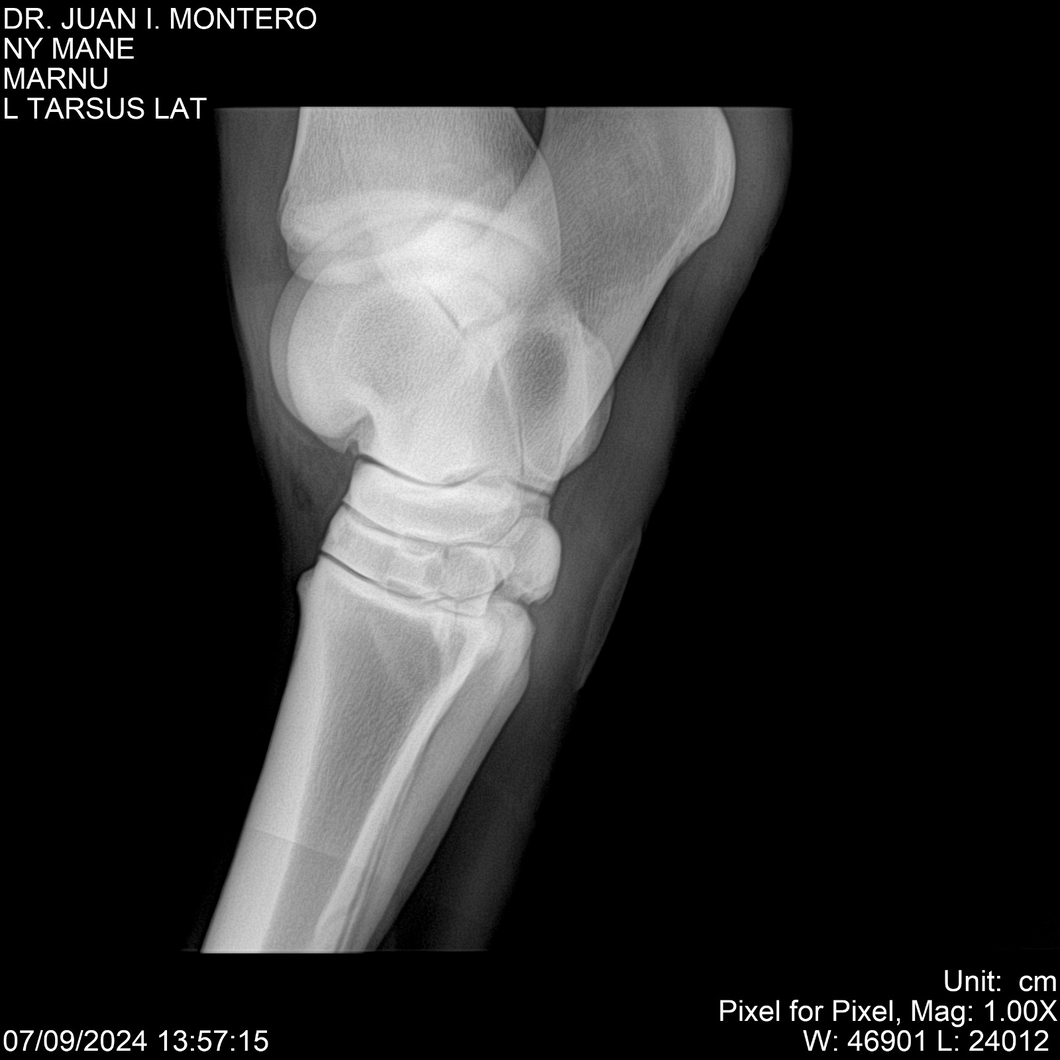

LOTE 20, NY MANE Lote Anterior Volver al remate Lote Siguiente Ficha Contacto Montevideo - Ficha del Lote Identificador: #282520 Categoría: Yeguarizos 76 Visualizaciones ClicData Contacto Empresa: Abelenda N. R., Walter Hugo Nombre*: Teléfono* : E-mail* : Mensaje Enviar Registrese gratis Este contenido Exclusivo está disponible sólo para usuarios registrados Ingresar